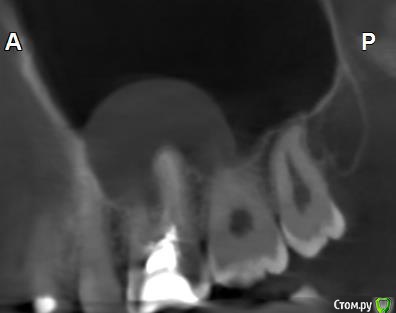

Здравствуйте! Верхний правый шестой зуб пломбировали 3 месяца назад. Примерно месяц назад он начал ныть, после насморка, сначала периодами, а теперь почти постоянно. При постукивание (ощущается не совсем так, как другие зубы) и пальпации десны он не болит. 2,5 месяца назад удаляли кисту из гайморовой пазухи. Может ли быть это какое-то воспаление и есть ли вероятность устранить его какими-нибудь антибиотиками, если да, то как, или может удалить зуб? Если есть воспаление, то какие могут быть последствия если не удалить зуб?

(Снимки с КТ, первые 8(Image) - сделаны сейчас,по 4 в разных проекциях, вторые 8(Before) - сделаны 5 месяцев назад до удаление кисты и повторного пломбирование зуба( до повторного пломбирование он реагировал на горячее, был запломбирован 3 года))